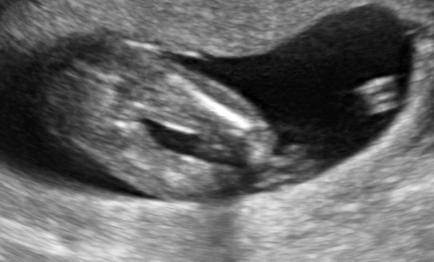

Pohlavie podľa ultrazvuku v 16tt

neboj, je mozne ze to tak nebude, mne dokazali v 20 tyzdni trikrat zmenit pohlavie :D v 16 je ten pipik taky malicky ze to vyzera ako kavove zrnko...uvidis neskor 🙂

Z dievčatka sa často "stane" chlapček, to naozaj ťažko poznať v 16 týždni. Ale opačne to nezvykne byť, skúsený doktor s dobrým usg a zvlášť 3Dzvykne už rozoznať semenníky. Mne povedala doktorka už v 12 týždni, že to bude na 80%chlapec, že už tam dačo rastie. No a v 16 tyzdbi to len potvrdila. No a mame ozaj chlapčeka 😃úplnú istotu aj tak budeš mat až po pôrode. Jednej známej celý čas vraveli, že bude mať dievčatko, poradňa, veľké usg a potom keď prišla už na kontrolu do nemocnice, pred pôrodom, tak ju primár "hodil" na ultrazvuk, pýta sa jej, či vie pohlavie a keď ona prikývla(ale nepovedala, že dievča) on s úsmevom "výborne, tak u nás porodíme toho krásneho chlapčeka" ona vytrestila oči, neverila, ani po pôrode nechcela chvíľu veriť, že skutočne jej "dievcatko" má pipik 😃😃😃

Prva v 16tt dievca a bolo dievca. A teraz v 2. v 16 tt chlapec a je to chlapec (potvrdene dna). Ale je vela pripadov, ze sa ukazalo az neskor, niektore az pri porode.